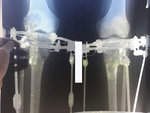

Дата операции 19.07.2017г

Дата снятия аппаратов 17.10.2017г.

Срок лечения 88 дней.